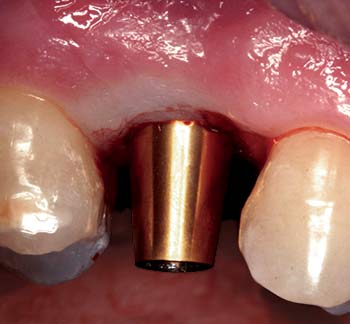

MinerOss Blend cases

grafting for implant placement

MinerOss Blend case 1

MinerOss Blend case provided by Dr. Bach Le